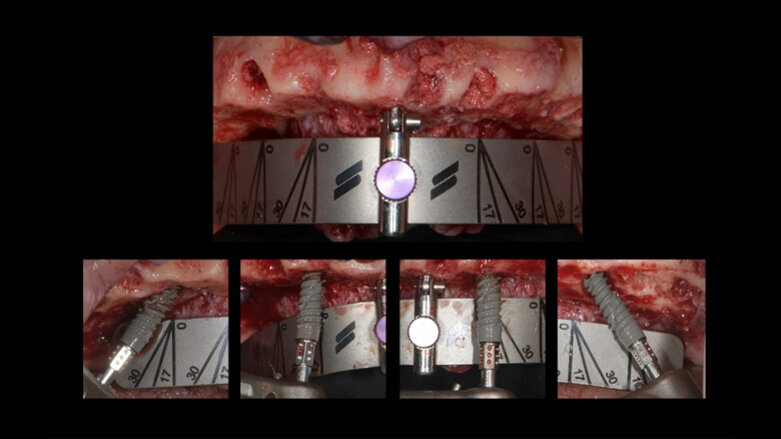

Full-arch surgery utilising the Smile in a Box system. (Image: Ricardo Mitrani)